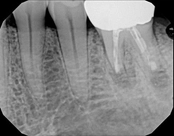

Missed canals and sclerotic orifices/canals:

4-month post-opIn this situation, some would say the canals are so “calcified” that root canal treatment can’t be done; or sometimes the canal can’t be found. And because of that the tooth would need an extraction and an implant. In some instances, root canal therapy can’t be done but that does not mean the tooth is a loss. The solution is micro-apical surgery, an apicoectomy.